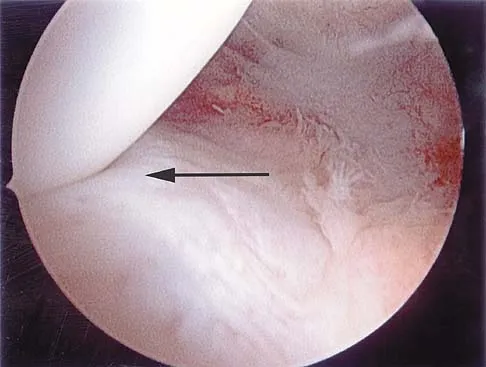

Question 98

Figure 43 shows an arthroscopic view of the posteromedial compartment of a patient's left knee using a 70-degree arthroscope placed through the intercondylar notch. The arrow is pointing to what structure?

Explanation